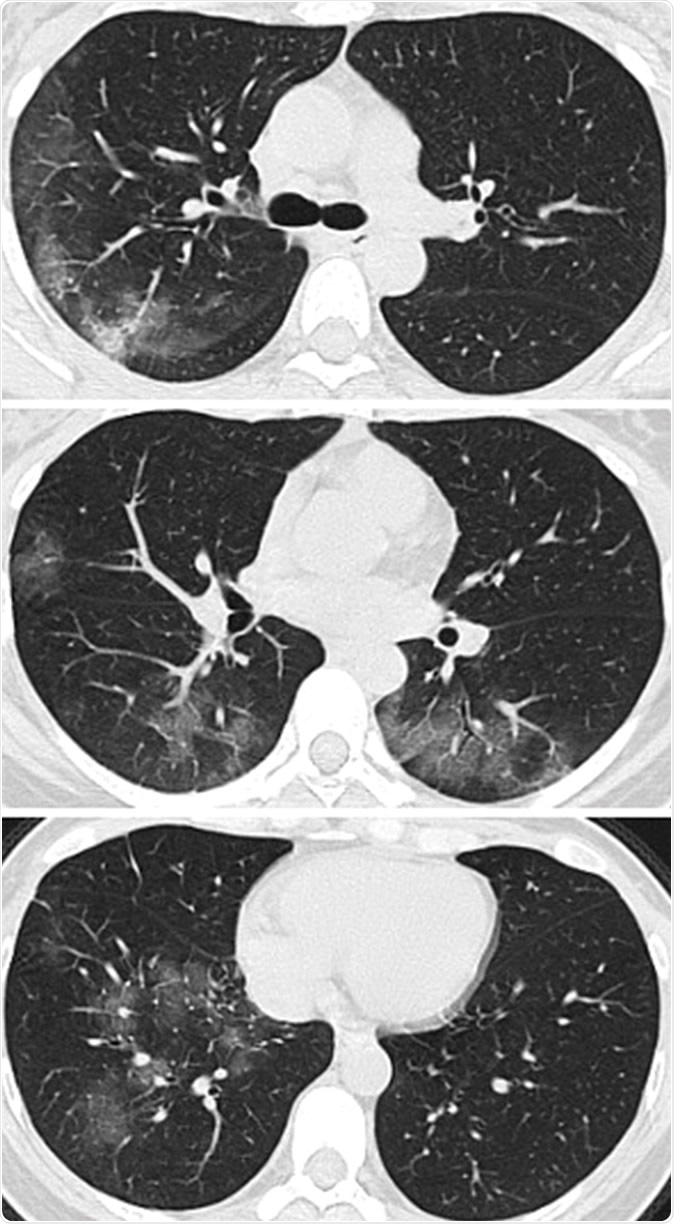

Images in a 41-year-old woman who presented with fever and positive polymerase chain reaction assay for the 2019 novel coronavirus (2019-nCoV). (a) Three representative axial thin-section chest CT images show multifocal ground glass opacities without consolidation. (b) Three-dimensional volume-rendered reconstruction shows the distribution of the ground-glass opacities (arrows). See also three-dimensional Movie (online).

The study examines the chest X-rays, and CT scans from over 20 patients aged 10-74 years, with symptoms of COVID-19. The scans showed inflamed lungs with ground-glass opacities, which look like white lung patches. These opacities are due to the partial clogging of the lung alveoli with tenacious mucus. Autopsies of Chinese patients who died of the illness because of breathing difficulties show lungs with minimal capacity for air inhalation due to the mucus accumulation.

The RSNA study shows how fluid accumulation in the lungs slowly worsens as the illness progresses, but then drains away if recovery begins until the lung spaces are completely clear.